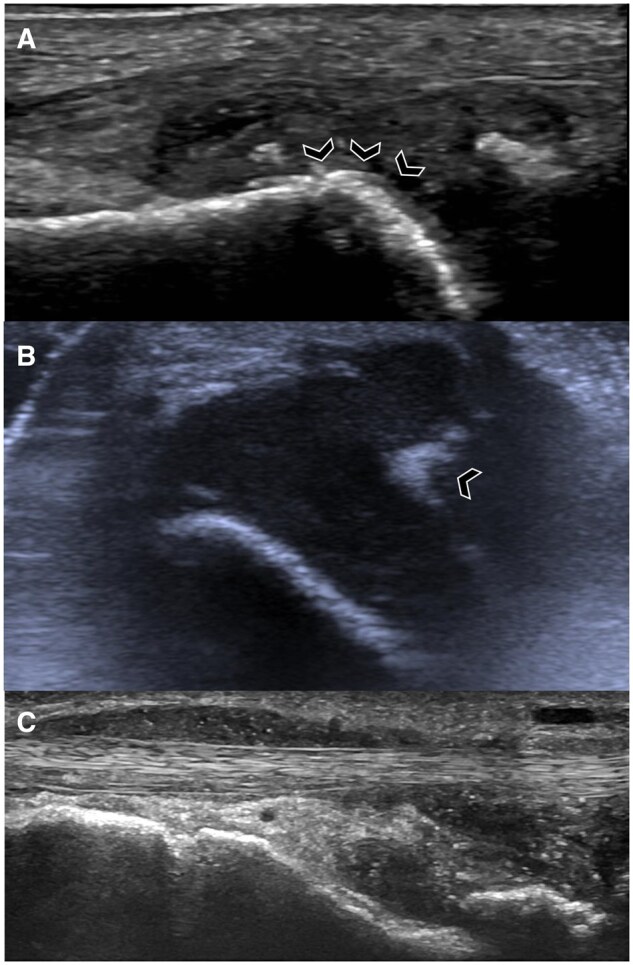

痛风是一种常见的全身性疾病,由尿酸钠(MSU)晶体沉积在关节和关节周围结构,导致反复发作的炎症。当晶体吸吸不可行、临床诊断不确定时,影像学对确定诊断有重要作用。每种成像方式都有其独特的作用。x光片可以显示痛风后期的特征性侵蚀和痛风。超声在痛风的诊断和评估中起着重要作用。双能计算机断层扫描(DECT)可以精确地显示MSU沉积物,并可以确定疾病负担。MRI可以评估非特异性炎症和结构改变。超声和DECT都被强调为诊断算法的一部分,随着最近的进展和证据,成像的作用正在扩大。这篇综述提供了一个以成像为中心的每一种模式的概述及其在痛风中的发展意义。

Gout is a common systemic disease defined by deposition of monosodium urate (MSU) crystals in articular and peri-articular structures, leading to recurrent bouts of inflammation. Imaging plays an important role in establishing the diagnosis when crystal aspiration is not feasible and the clinical diagnosis is uncertain. Each imaging modality has a unique role. Radiographs can demonstrate characteristic erosions and tophi in later stages of gout. Ultrasound has a major role in the diagnosis and assessment of gout. Dual-energy computed tomography (DECT) enables precise visualization of MSU deposits and can determine disease burden. MRI can assess for non-specific inflammatory and structural changes. Both ultrasound and DECT are emphasized as part of diagnostic algorithms and the role of imaging is expanding with more recent advancements and evidence. This review provides an imaging-centric overview of each modality and its evolving significance in gout.